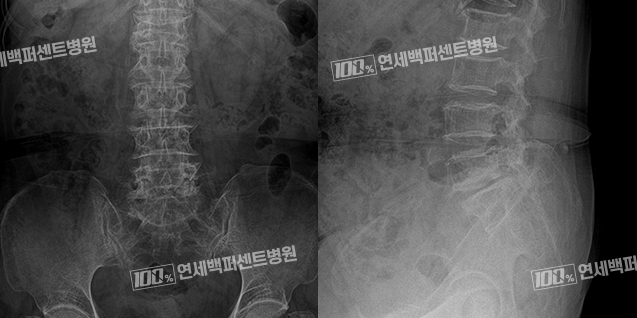

척추전방전위증 치료 Before & After

치료 전

척추 유합술 후